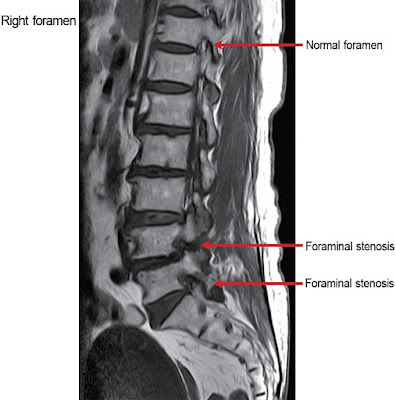

O segundo espaço é o forame intervertebral, que é esse espaço ao lado das vértebras por onde passam as raízes nervosas. Também é chamada de estenose lateral. Esse espaço é formado pela sobreposição de uma vértebra na outra.

estenose foraminal degenerativa